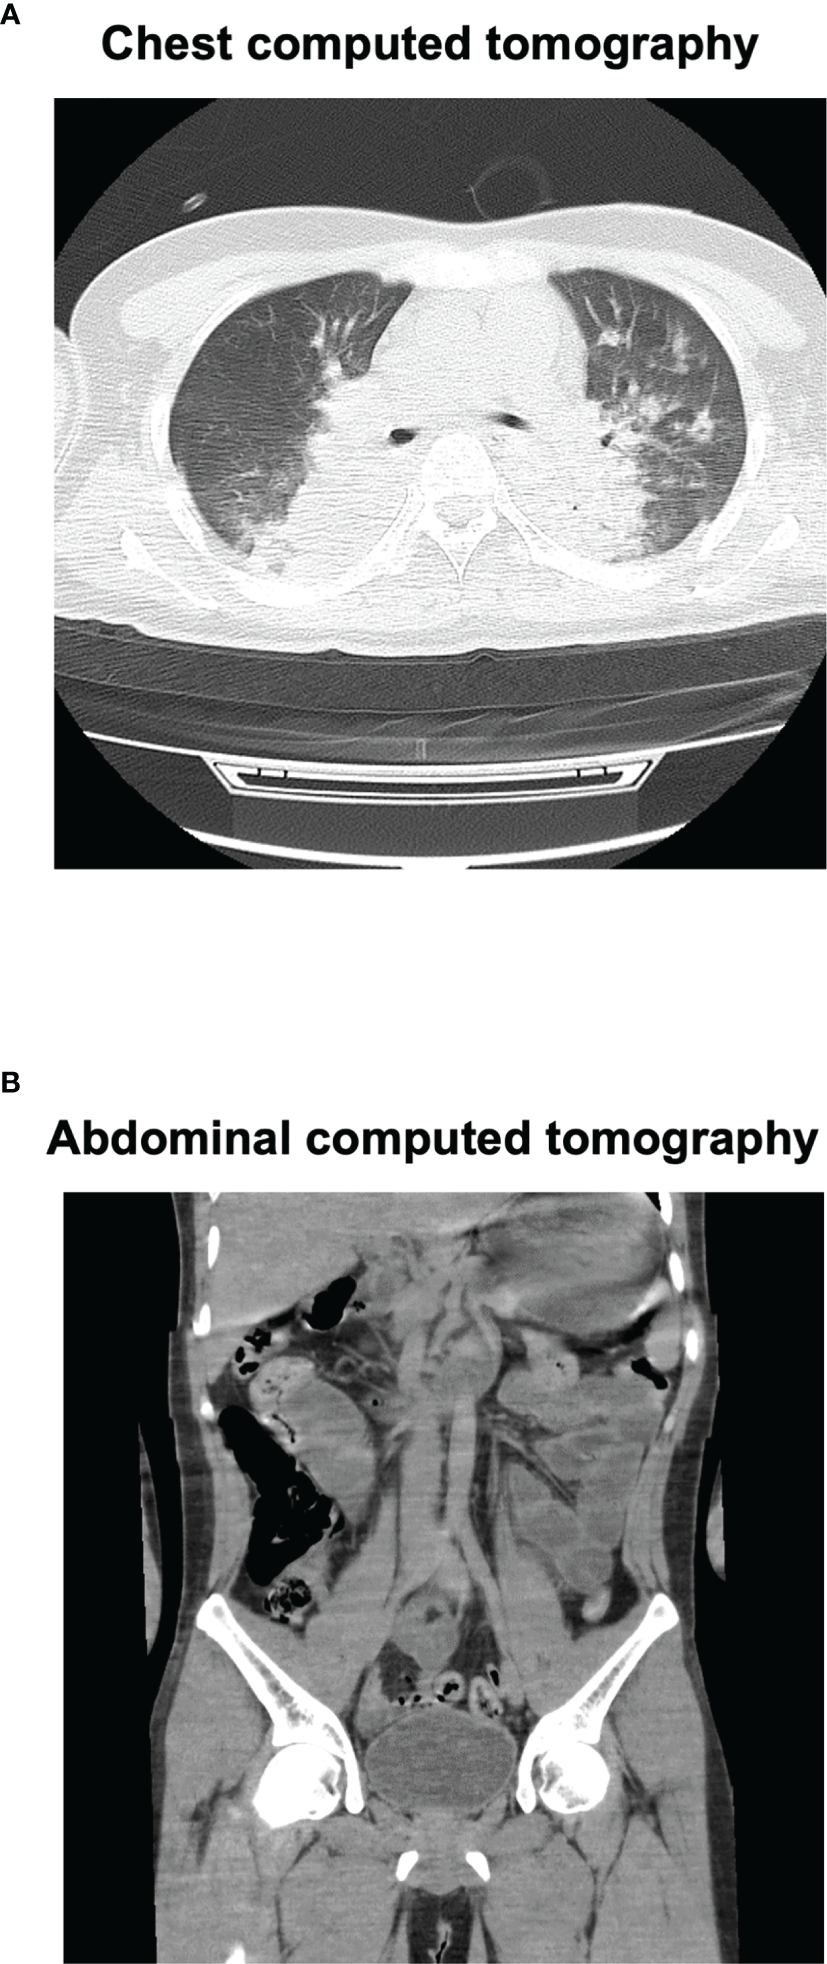

Figure 1

Chest and abdominal computed tomography (CT) on admission. Chest CT (A) revealed marked pleural effusion and pulmonary edema. Abdominal CT (B) revealed marked intestinal edema.

A 27-year-old Japanese man was brought to the emergency room with coma. He was diagnosed as having schizophrenia at the age of 13 and as having autism spectrum disorder at the age of 18. The medication at that time was 50 mg/day of atomoxetine, 5 mg/day of risperidone and 3 mg/day of guanfacine, although risperidone was decreased from 9 to 5 mg and guanfacine was increased from 2 to 3 mg 35 days before. He had been drinking over 4 L of water for the last few weeks. His impaired consciousness level was 3 points (E1V1M1) of the Glasgow coma scale (GCS). His vital signs were as follows: temperature, 39.1°C; blood pressure, 174/98 mmHg; heart rate, 95 beats/min; oxygen saturation, 92% (under 9 L of O2 supply). Table 1 shows laboratory data in emergency room. He suffered from abnormal balance of electrolytes. As shown in Table 1, he had significant hyponatremia and hypochloremia with normal potassium concentration, and reduction of blood osmotic pressure. His inflammation markers were markedly elevated. In addition, he suffered from rhabdomyolysis. Indeed, his creatine kinase, myoglobin and urinary myoglobin levels were significantly high. As shown in Figure 1, his head computed tomography (CT) (Figure 1A) revealed severe cerebral edema. In addition, significant fluid retention was observed throughout the body, namely, pleural effusion, pulmonary and intestinal edema (Figures 1A, B). We evaluated the causes of hyponatremia in this patient. Since antidiuretic hormone (ADH) level was elevated to 0.8 pg/ml when sodium level was 109 mmol/L, we diagnosed him with syndrome of inappropriate secretion of ADH (SIADH). Based on these findings, we thought that he probably suffered from severe cerebral edema which was induced by hyponatremia associated with NMS and SIADH. In addition, rhabdomyolysis and NMS was diagnosed necessitating comprehensive therapy in intensive care unit (ICU).